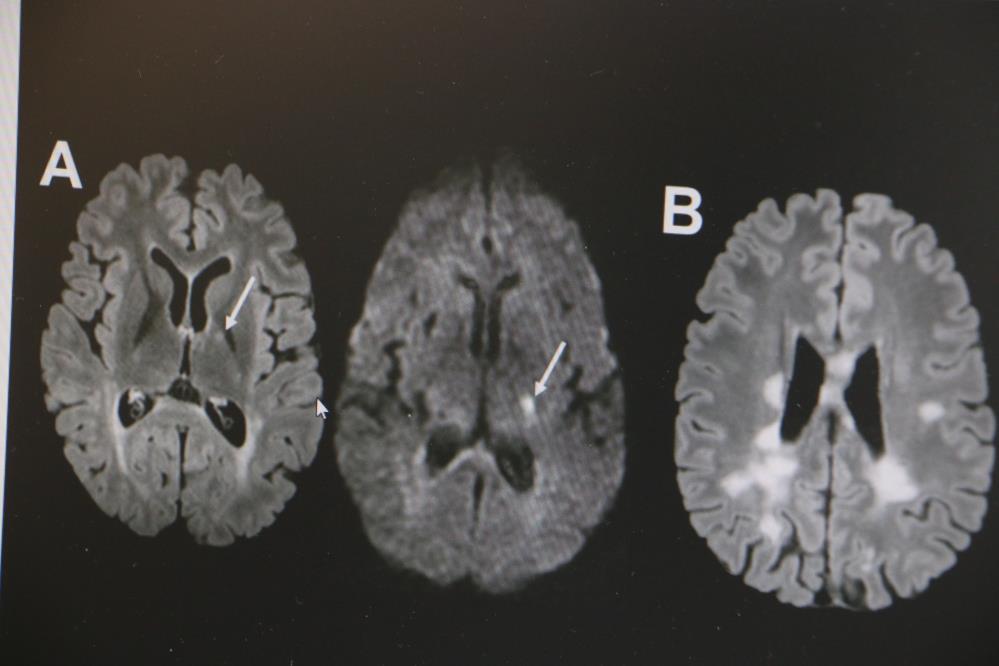

MS hastalığının kadın popülasyonunda daha sık görüldüğünün altını çizen Demir, "Kadınlarda erkeklere göre bu hastalık yaklaşık 2 kat daha sık görülmekte. MS hastalığı özellikle ataklarla seyreden bir hastalıktır. Hastaların yüzde 85’inde relapsingremitting form dediğimiz atak formuyla seyretmektedir. MS hastalığının tanısı klinik olarak kesin tanı konulabilse de günümüz şartlarında MR çekilmeden kesin tanı konulmaması önerilmektedir. MS hastalığının tedavisine gelecek olursak, kesin bir tedavisi yoktur. Ancak son 10 yılda çok sayıda ilaç kullanıma girmiştir. Bu açıdan MS hastalığı kontrol edilebilir bir hastalıktır. MS hastalığına bağlı ataklara karşı hastalara steroid tedavisi vermekteyiz. MS hastalarında görülen her şikayet atak olmayabilir. Özellikle idrar yolu enfeksiyonu, üst solunum yolu enfeksiyonu, aşırı egzersiz durumlarında, sıcak bir ortamda bulunma gibi durumda hastalarda ısı artışına bağlı olarak daha önceden var olan semptomlarda kötüleşme olabilir. Bunlar daha çok yalancı atak diyebiliriz. Ancak atak diyebilmemiz için şikayetin en az 24 saat sürmesi gerekmektedir" ifadelerinde bulundu.